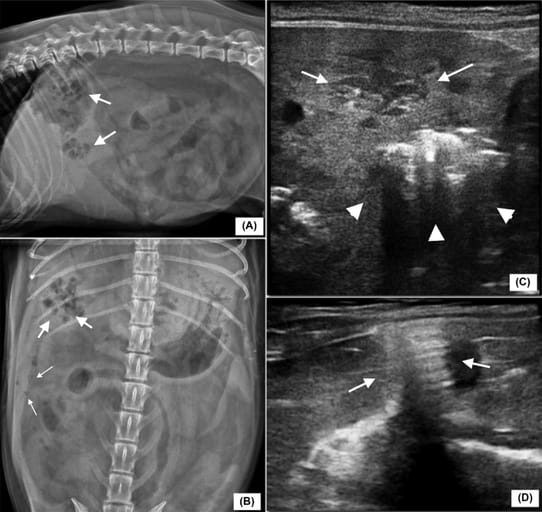

Right lateral (A) and ventro-dorsal (B) radiographic views of the abdomen of a 12-year-old spayed female mixed breed dog with suppurative hepatitis (96 kVp, 10.00 mAs): gas lucencies are seen superimposed to the right and central hepatic silhouette (arrows) and in the pertioneal space (small arrows). Ultrasonographic image of the liver (C) in the same dog (longitudinal plane, 7.5 MHz linear array probe): hypoechoic lesion (arrows) and multiple hypoechoic foci with reverberation artifacts (arrowheads) within liver parenchyma indicating parenchymal emphysema. Pneumoperitoneum is seen on ultrasound (D) as thickening of the peritoneal stripe with reverberation artifacts (arrows)